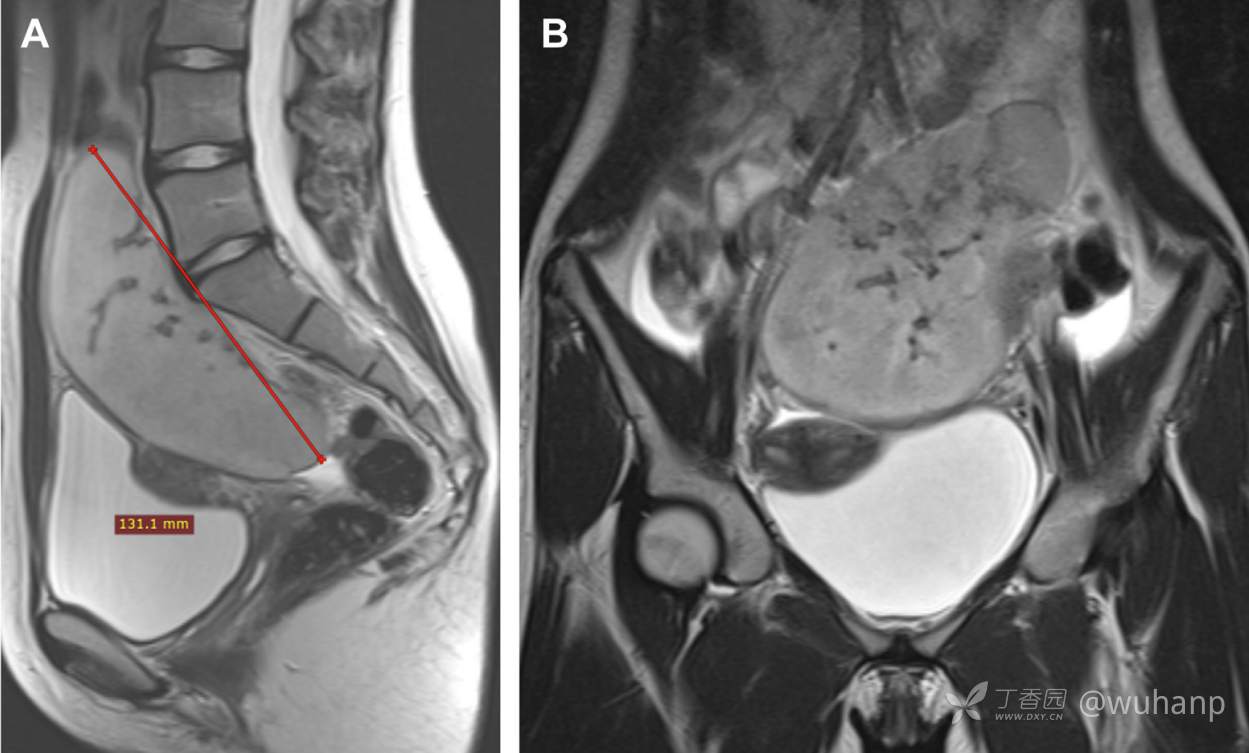

腹部MR检查提示盆腔内巨大肿块,大小约 131×92×40 mm,位于Douglas腔内(图A,图B)。

A 卵巢癌 B 畸胎瘤 C 腹腔肉瘤 D 脾脏